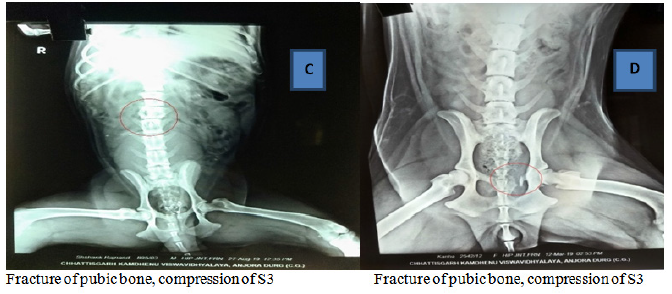

On survey radiography the patient were screened for the vertebral injuries as described in Table 1 and Figures 1A–1F, first case reflecting displacement of L3 in relation to L2, second case showed complete fracture between T12-13, third patient revealed compression in L3, fourth case had fracture of left pubic bone with compression of S3 and fifth and sixth case showed abnormality in both L1-2 and caudal 3 vertebrae. Plain radiography supports findings, formal interpretation for immobilizing the patient appropriately. The failure to adequately immobilize the spine owing to mechanism of injury diagnosis is a pitfall.9

Figure 1A–1F Radiographic investigations.